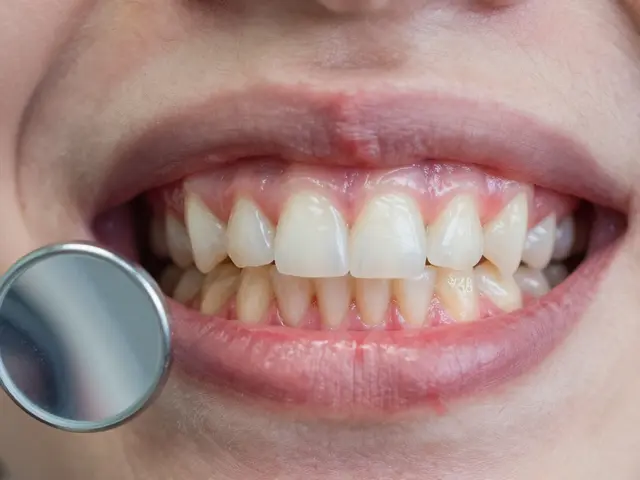

Nejčastější příběh: dítě ve 18 letech začne cítit bolest v zadní části čelisti. Otevře ústa, ale nic nevidí. Dásně jsou zarudlé, otok, až se bolejí i uši. To je perikoronaritida - zánět tkáně kolem částečně vyrůstajícího zubu 48.

Nejčastější příčina: jídlo a bakterie se zaseknou pod dásní, která překrývá zub. Z toho vzniká infekce. Vypadá to jako malý absces. A není to jen bolest. Může se rozšířit do krku, do uší, dokonce do klíční kosti.